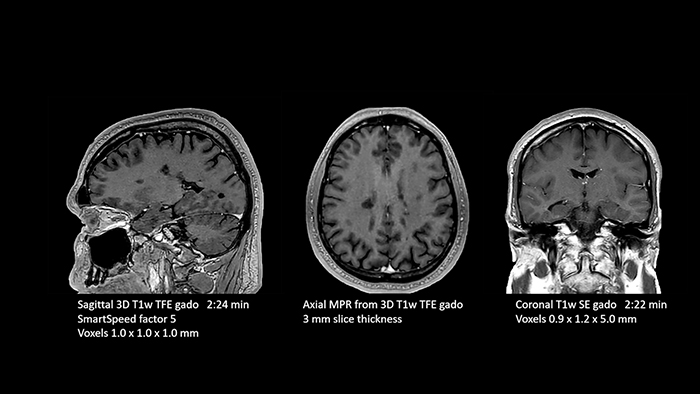

Dr. Schröter points out that a more confident diagnosis requires high-quality images with more diagnostic information. “Philips SmartSpeed provided that to us. AI denoises the clinical images without losing any important data, resulting in high-resolution images. It keeps all the information we need and makes the images better.

We can apply SmartSpeed to almost all sequences. That is a big step forward! We use it for example in 3D imaging and in diffusion-weighted imaging, to dramatically reduce scan time or increase image resolution, which is quite useful.

There are small lesions that we would certainly have seen without SmartSpeed, however it would have taken us longer to properly diagnose. In 3D MSK images with extremely high resolution, we uncover the finest anatomical structures and can thus report very detailed findings.”